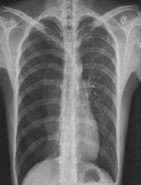

病史:男性,65岁,突感胸闷气促1小时。诊断:

○ 右侧气胸

○ 右侧大叶性肺炎

○ 右侧胸腔积液

肺结核

○ 右侧肺癌